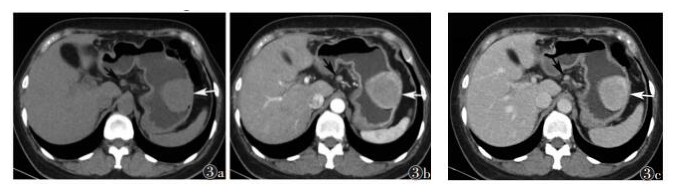

| 图 3 女,48岁 图 3a CT平扫示胃大弯侧类圆形软组织密度肿块影,腔内生长,密度尚均匀,边界清晰(白箭) 图 3b 增强扫描动脉期不均匀轻度强化(白箭) 图 3c 静脉期瘤体强化更明显(白箭);腹膜后肿大淋巴结,强化均匀(黑箭) |

2.2 MSCT表现8例中,7例表现为圆形或类圆形肿块,其中1例边缘可见小凹陷;另1例肿块较大,边缘可见浅分叶。3例向腔内生长,2例向腔外生长,3例腔内外生长。平扫CT值30~60 HU,增强扫描:1例在动脉期明显均匀强化(图 1);2例肿块内部发现小片状低密度区,增强扫描强化不均匀(图 2);5例均呈均质密度,动脉期轻度强化,静脉期轻中度强化。1例伴胃周淋巴结肿大(图 3),病理证实肿大淋巴结为反应性增生,并非转移。所有患者均未发现钙化灶、出血、邻近结构侵犯及腹水等情况。